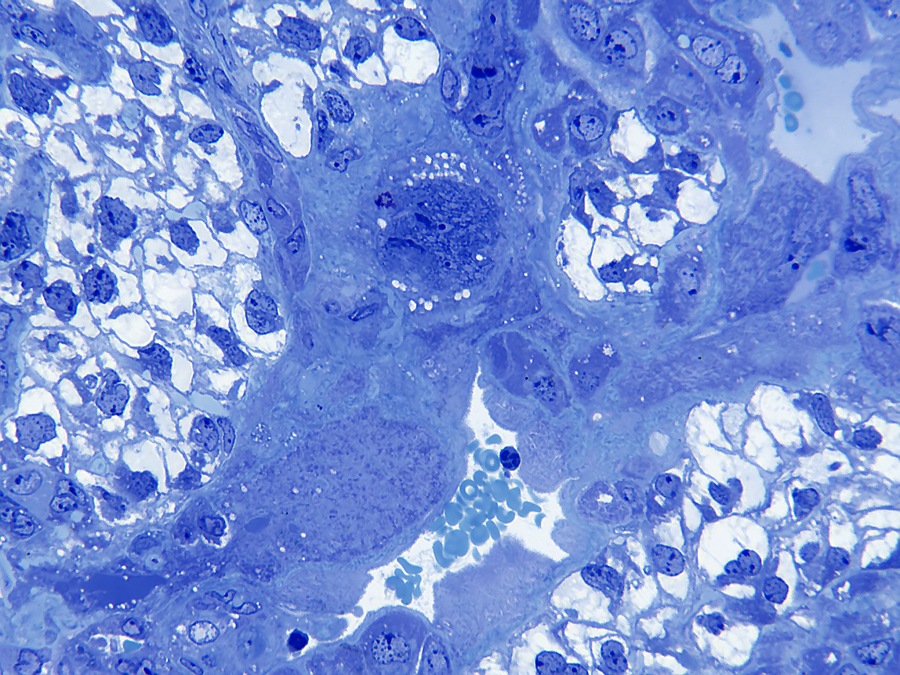

Trophoblast giant cells in the placenta of a mouse embryo. More information can be found in the specimen description.